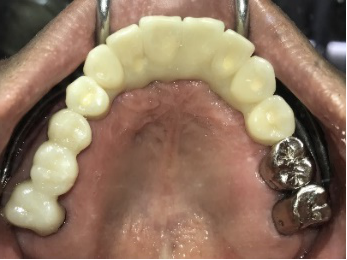

男性Kさん 50代(インプラント)

歯がグラグラするところ、むし歯のところ、しみるところ、被せ物がとれたところ、歯茎が腫れて血が出るところ、歯が抜けているところがある。すべて治したい。

治療内容

残っている歯を抜歯し、上下インプラント治療をしました。

所感

歯周病が進行している歯、むし歯が進行している歯がほとんどで、レントゲンを撮り、詳しく診てみると、ほとんどの歯を保存することができないことがわかりました。抜歯後は、入れ歯かインプラントの方法があります。治療開始前に患者さんに詳しく現状を説明し、治療法についてじっくり相談しました。自分の歯と同じような感覚で食事できるインプラント治療を選択されました。治療後、表情がとても明るくなり、口元がとても自然で10歳以上若返ったように感じました。「時間はかかりましたが、インプラントにして本当に良かったです!」と素晴らしい笑顔でお話ししてくださいました。

上顎:¥3,280,000(税込)

下顎:¥3,280,000(税込)